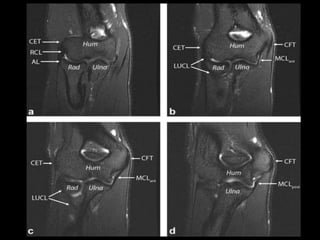

Elbow Joint.